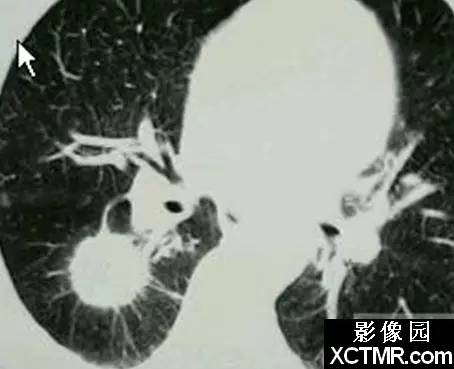

影像表现:印戒征见于胸部CT扫描。它是由一小圆形软组织密度影邻接一围绕大圆形低密度空气影的环状软组织密度影构成。

说明:在横断面CT扫描上,环状软组织密度影代表扩张的支气管壁,圆形低密度空气影代表扩张的支气管内气体。与环邻接的圆形软组织密度影代表与扩张支气管伴行的肺动脉的横断面影像。

讨论:印戒征是支气管扩张患者的CT表现。支气管扩张定义为不可逆性支气管异常扩张。扩张的支气管一般在中等大小的支气管最广泛。同时,可以发生支气管肌肉萎缩,支气管壁破坏,支气管周围炎症和纤维化。由于纤毛活动减弱和支气管动力学异常,大量粘液聚集在这些扩张的支气管内。

支气管扩张常由于坏死性病毒性或细菌性支气管炎后支气管壁损伤引起,常发生在婴幼儿期。支气管扩张也可发生在阻塞的支气管远端,当分泌物聚集在阻塞支气管的远端导致它们扩张。进展期肺纤维化或放射性肺损伤也能引起支气管扩张。囊性纤维化;通气压增高,例如正压通气;纤毛功能紊乱,如Kartagener综合症以及各种免疫缺陷都同样与支气管扩张有关。

支气管扩张一般分为三种形态学类型。柱状支气管扩张,最轻的形式,特征是支气管轻度均匀扩张。静脉曲张样支气管扩张是指支气管中度扩张,呈不规则串珠样。囊状扩张是最严重的,支气管显著囊样扩张,伴有数量不等的分泌物池。

支气管扩张的临床表现常为非特异性的。慢性咳嗽,过量痰,反复肺部感染,咯血都可以出现。尽管胸部平片可以显示扩张的支气管,CT可以提高我们发现支气管扩张的能力。事实上,CT已经取代支气管造影,成为评估支气管扩张可能的研究选择。薄层CT对发现支气管扩张的敏感性为87%-97%,特异性为93%-100%。

支气管扩张的胸部平片表现包括扩张的充气支气管,支气管壁增厚,肺实质体积减小,支气管聚集。也能见到由于肺炎或纤维化所致的肺透亮度异常。在薄层CT可见到支气管扩张,缺乏支气管尖端变细,在胸膜1cm内见到支气管,支气管壁增厚和印戒征等。支气管与动脉比率随不同参数而变化,例如CT扫描的海拔高度,因此,仅发现支气管直径大于相邻动脉不足以诊断支气管扩张。

以CT为基础诊断支气管扩张有几个缺陷,包括呼吸运动或心脏搏动所致的运动伪影,与层厚和窗相关的技术因素。因此常需要用薄层CT来诊断支气管扩张。